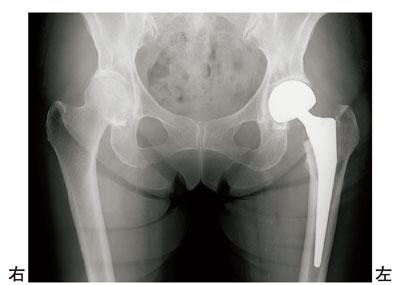

87歳の女性。転倒して左股関節痛を訴え、入院となった。受傷後2日目に後方侵入法で手術を受けた。術後のエックス線写真を示す。正しいのはどれか。

1

臥床時には股関節を内転位に保つ。

2

靴下の着脱は股関節外旋位で行う。

3

術後1週から大腿四頭筋セッティングを開始する。

4

術後2週から中殿筋の筋力トレーニングを開始する。

5

術後3か月は免荷とする。